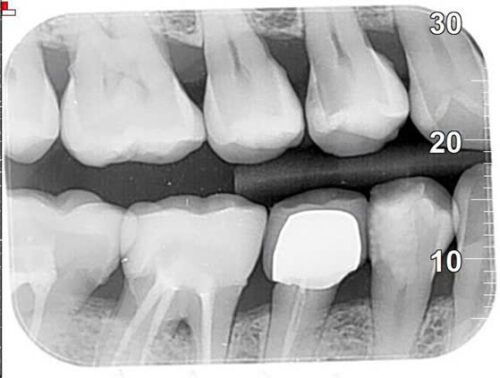

Kiểm tra lại bằng cách chụp phim cánh cắn – “tiêu chuẩn vàng” trong chẩn đoán sâu răng mặt bên: Có tổn thương mất khoáng vùng R14-15

Sau khi làm sạch lỗ sâu:

Kết quả điều trị với vật liệu có phóng thích Fuour